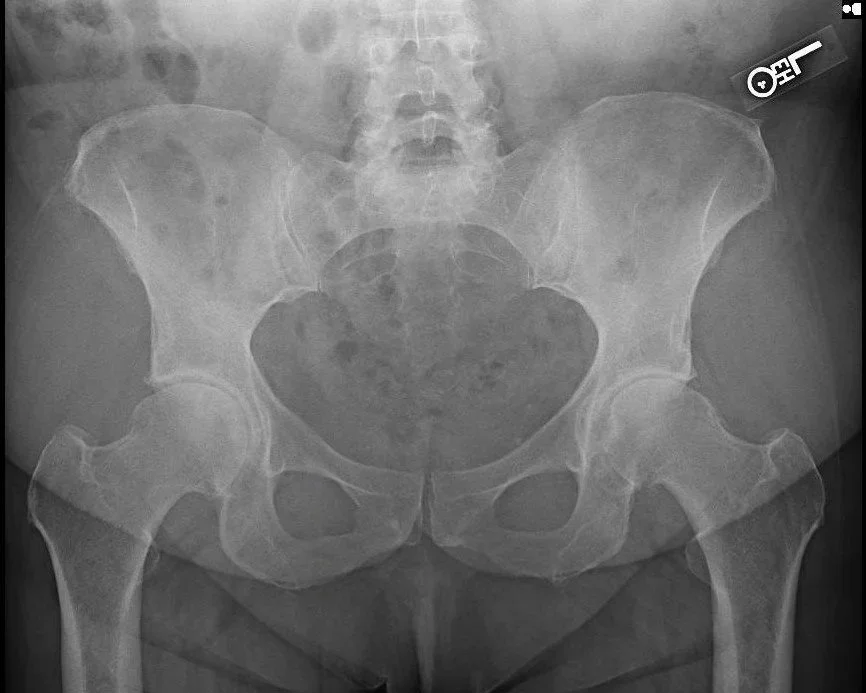

Useage of X Ray Intraop: Easy to get a perfect AP x ray during surgery which allows for more accurate placement of components in the ideal position